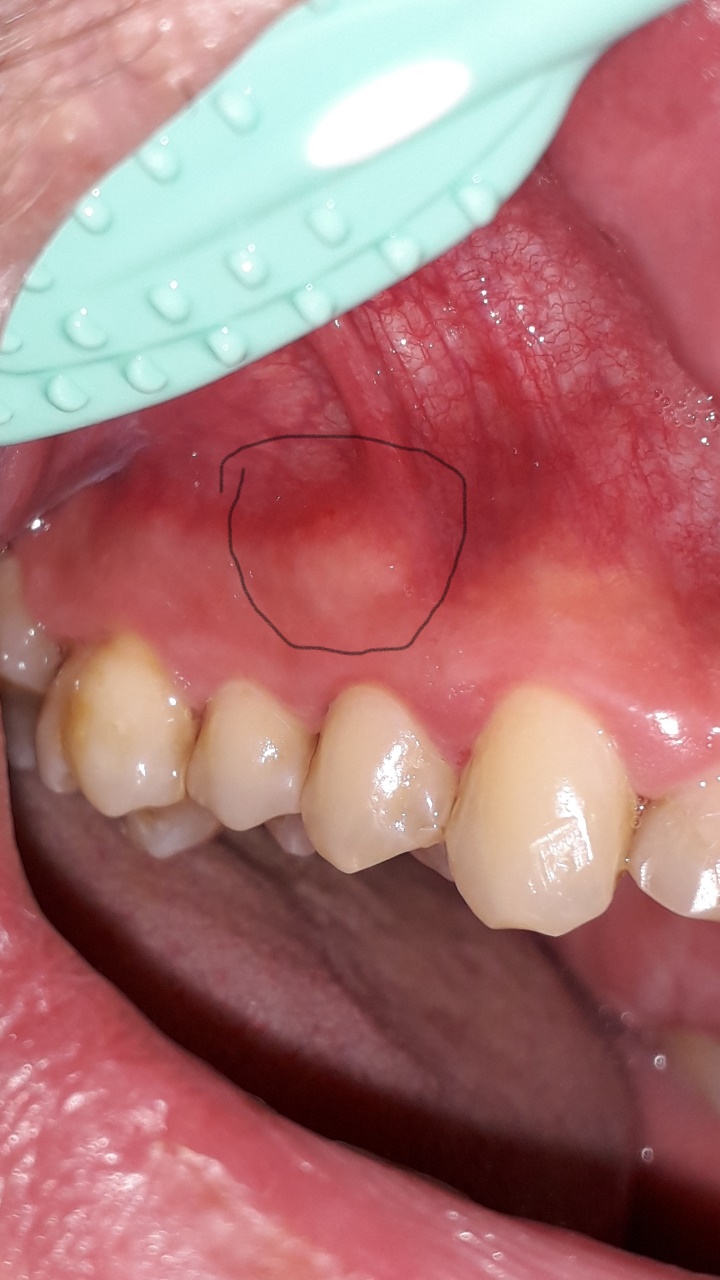

Knubbel neben Zähnen rechts und links? (Gesundheit und Medizin, Zahnarzt)